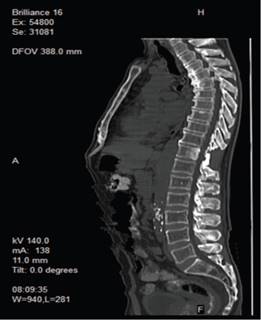

Estudios de orina revelaron hematuria con 28-30 eritrocitos por campo y bacterias escasas de etiología Klebsiella spp. Se realizó Tomografía Axial Computarizada (TAC) de abdomen y pelvis, mostrando enfermedad diverticular, y Resonancia Magnética (RMN) de columna que evidenció lesión tumoral sólida en T11, con compresión del cordón medular (ver imágenes 1 y 2) y adenomegalias en T9 y T10. Además, se detectaron hemorroides grado I y osteoporosis con desmineralización del 39%.

Figura 1: Infiltración metastásica en T11 (Corte sagital - Resonancia Magnética) Resonancia magnética sagital que muestra una infiltración metastásica en el cuerpo vertebral de T11, posterior a resección quirúrgica de su apófisis espinosa. Autoría: Clínica del Valle